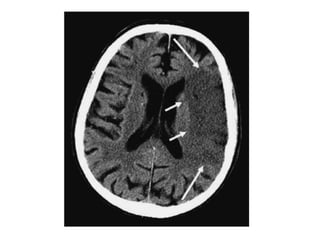

c) Hyperdense artery :

-Represents acute thrombus within the vessel

-Most commonly recognized with basilar and

proximal MCA thrombosis

-False positives can occur if a vessel is partially

calcified or if the haematocrit is raised (i.e.

polycythaemia)

-On the left a patient with a dense MCA sign

-On CTA : occlusion of the MCA is visible